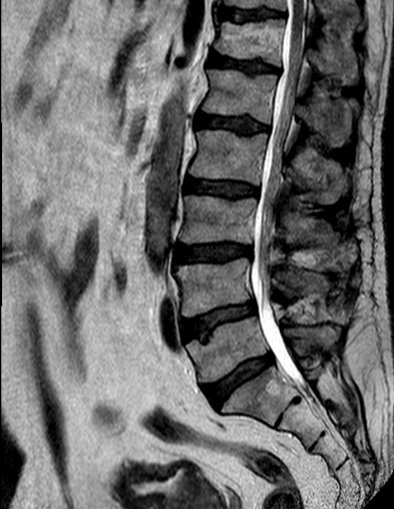

Paciente de 63 años con clínica de claudicación de la marcha.

El paciente está asintomático en decúbito y la RM se obtiene en decúbito. La fisiopatología de la claudicación neurógena de la marcha es mecánica: de pie o andando la carga de los discos se incrementa, además, la posición erguida provoca frecuentemente que se incremente la lordosis respecto al decúbito por lo que los ligamentos («amarillos» o interlaminares e interespinosos) protruyen en el canal. La descompresión interlaminar no modifica la distribución de cargas, pero al eliminar las partes blandas que protruyen se mejora la compresión y la claudicación neurógena de la marcha.

Preoperatorio